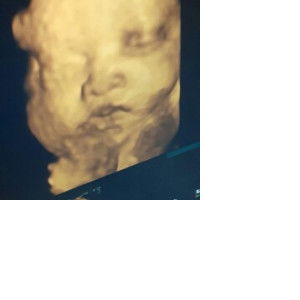

Bun, kalau usia 5 minggu keluar flek coklat bahaya gak sih? cuma sehari doang, dikit

saya jg pernah sampe kluar darah trs flek terus2n dri hamil 5w sampe 10w. trs periksa alhmdlh gpp stlh usg, trkdg ada yg emg gtu. yg penting jgn trlalu capek trlalu kpikiran, dan kalo sampe keluar darah kyk haid bnya baru itu bahaya gtu kata dkternya. itu pngalamn saya sih bun